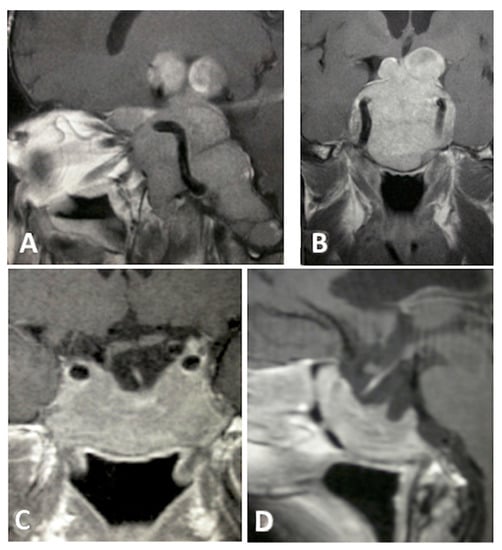

Among the 96 patients included, 55 were men (57.3%) and 41 were women (42.7%), and the mean age was 52.2 years (range 26–81 years). Gender and age were not significantly associated with EoR rate (p = 1.763) or hospital length of stay. Mean cranio-caudal diameter of lesion was 46.5 mm (range 41–61 mm). According to Knosp [8] grading scale, 30 (31.2%) were classified as grade 0; 24 (25.0%) grade 1; 19 (19.8%) grade 2; 9 (9.4%) grade 3 and 14 (14.6%) grade 4. Endocrinological screening confirmed the non-functioning status in all patients included in the study. Seventy-eight patients (81.2%) presented with visual field defects, 9 of whom (9.4%) also had visual acuity impairment. Fifty-three patients (55.2%) presented with various degree of anterior pituitary insufficiency: 27 had panhypopituitarism, 14 had combined corticotropic and thyrotropic insufficiency, 6 had isolated corticotropic insufficiency, 3 had isolated thyrotropic insufficiency and 3 isolated gonadotropic insufficiency. Twelve patients (12.5%) had headaches and 3 (3.1%) presented drowsiness associated with hydrocephalus. According to intraoperative assessment of lesion consistency, 50 GPAs (52.1%) were soft, whereas 46 GPAs (47.9%) were firm/fibrous. Thirty-one GPAs (32.3%) were deemed to have significant vascularization due to profuse intraoperative bleeding impairing visualization through the endoscopic lens and requiring more than 20 mL of advanced hemostatic matrix, whereas the remaining 65 GPAs (67.7%) did not. Interestingly, our results are in keeping with the data reported by previous studies [11,12], confirming that 2/3 of GPAs are not highly vascularized. EoR was classified as follows: GTR in 34 cases (35.4%) (Figure 1), NTR in 12 cases (12.5%) (Figure 2), and STR in 50 (52.1%) (Figure 3 and Figure 4).

Figure 4. T1- weighted contrast-enhanced MR images. Preoperative sagittal (A) and coronal (B) views showing a giant pituitary macroadenoma, Knosp grade 3, extended to the right maxillary sinus, subfrontal, and clival areas. Three-month postoperative sagittal (C) and coronal (D) views showing STR with residual tumor left in the clival, right subfrontal, and right orbital areas.